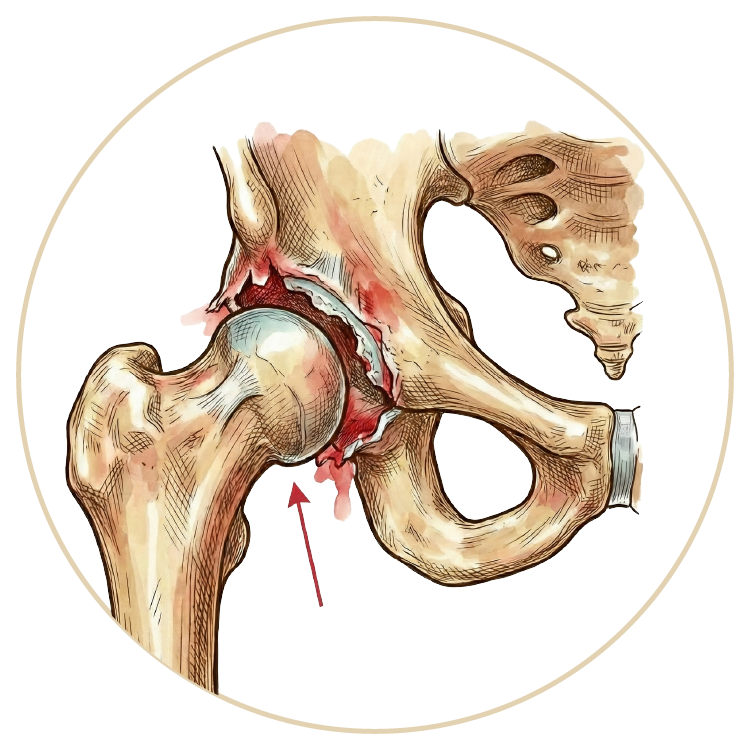

Kalça Hastalıkları ve Tedavileri

Kalça Hastalıkları ve Tedavileri

Travmatik Kalça Çıkığı